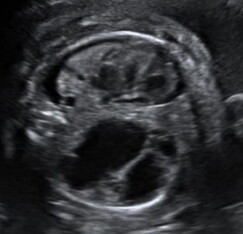

La CPAM viene agevolmente diagnosticata mediante l’esame ecografico in cui appare come un’area iperecogena disomogenea con all’interno possibili aree cistiche anecogene di diverse dimensioni, contenenti liquido. Tra le diverse classificazioni esistenti, quella attualmente più utile in ambito ecografico soprattutto per il suo significato prognostico, distingue le forme di CPAM in macrocistiche e microcistiche.

Immagini ecografiche di CPAM di tipo macrocistico (A), microcistico (B) e misto (C)